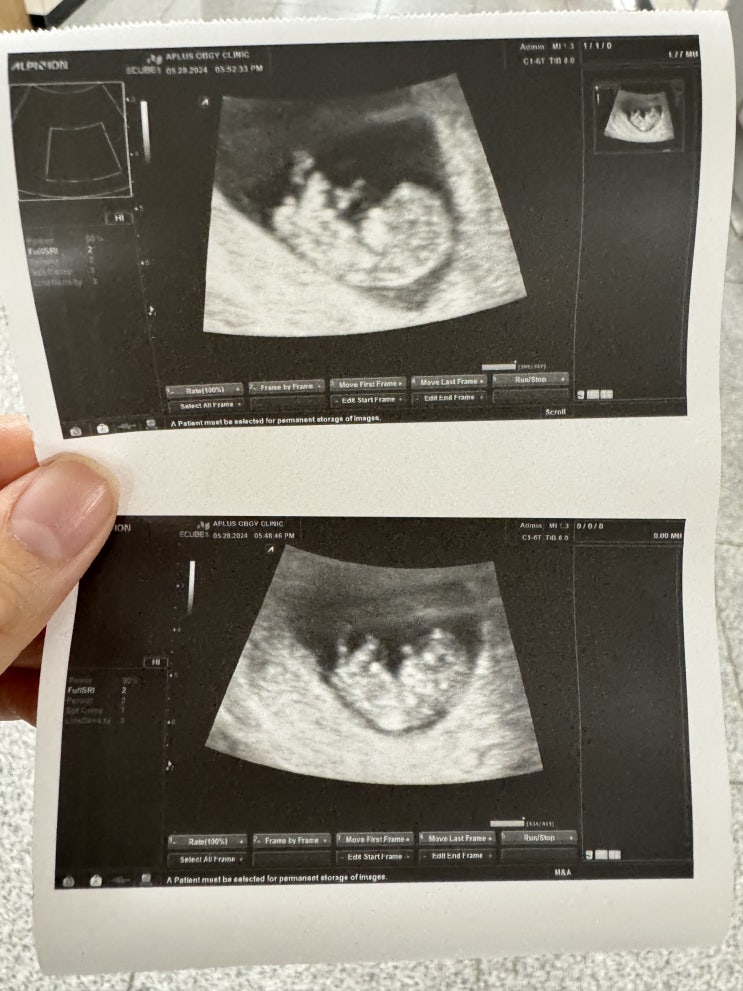

✨임신19-23주차일상/정밀초음파/전치태반/임산부수영/

20주-24주차에는 태아 정밀 초음파를 보는 시기예요 1차검진때 목투명대 등 기본 검사를 했다면 정밀초음파...